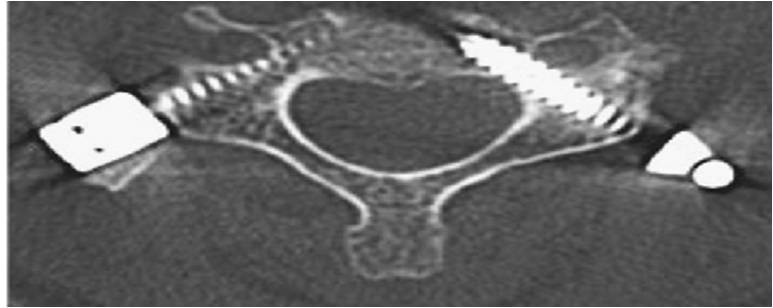

- α

- β

Εικόνα 7 (α,β): Διαυχενικές βίδες που έχουν τοποθετηθεί με καθοδήγηση από το σύστημα πλοήγησης O-arm σε αυχενικό σπόνδυλο. Εδώ απαιτείται μέγιστη ακρίβεια για την όδευση της διαυχενικής βίδας καθώς η διάμετρος του μίσχου είναι πολύ μικρή περίπου 4mm.